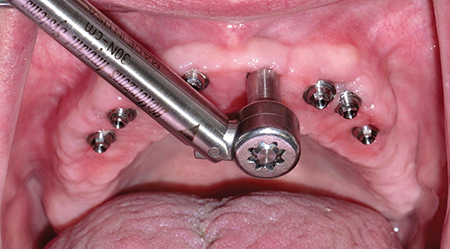

The following case presentation will illustrate an anterior maxillary reconstruction with the use of dental implants and fixed prosthodontics. Our patient (P.C.) presented to the office with the pre-existing dental treatment done over 10 years ago as illustrated in Figures 1 and 2. Due to a large diastema between 11 and 21, the previous practitioner … Read more